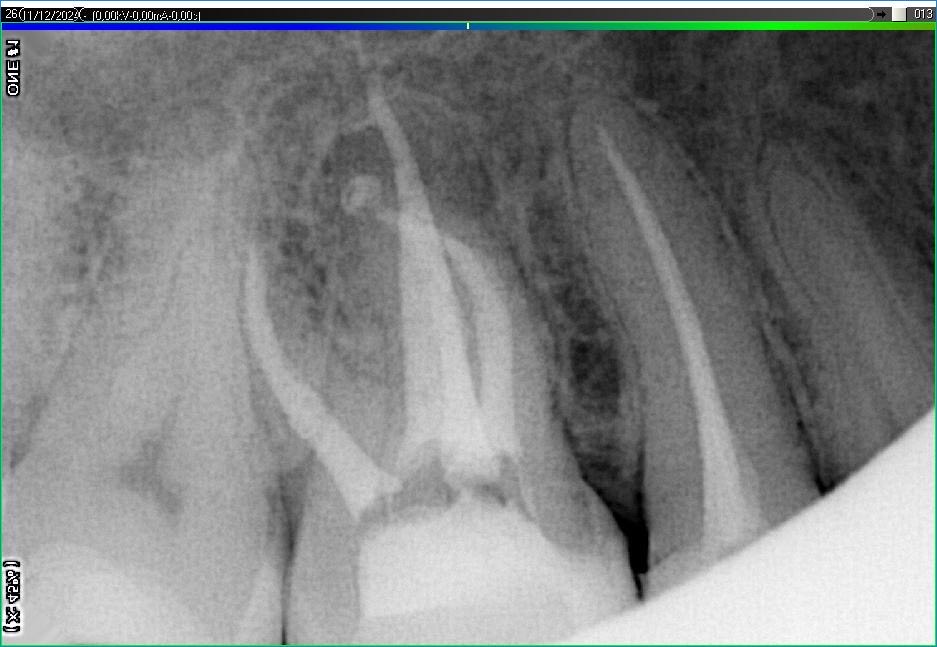

Вилучення інструменту з каналів зуба